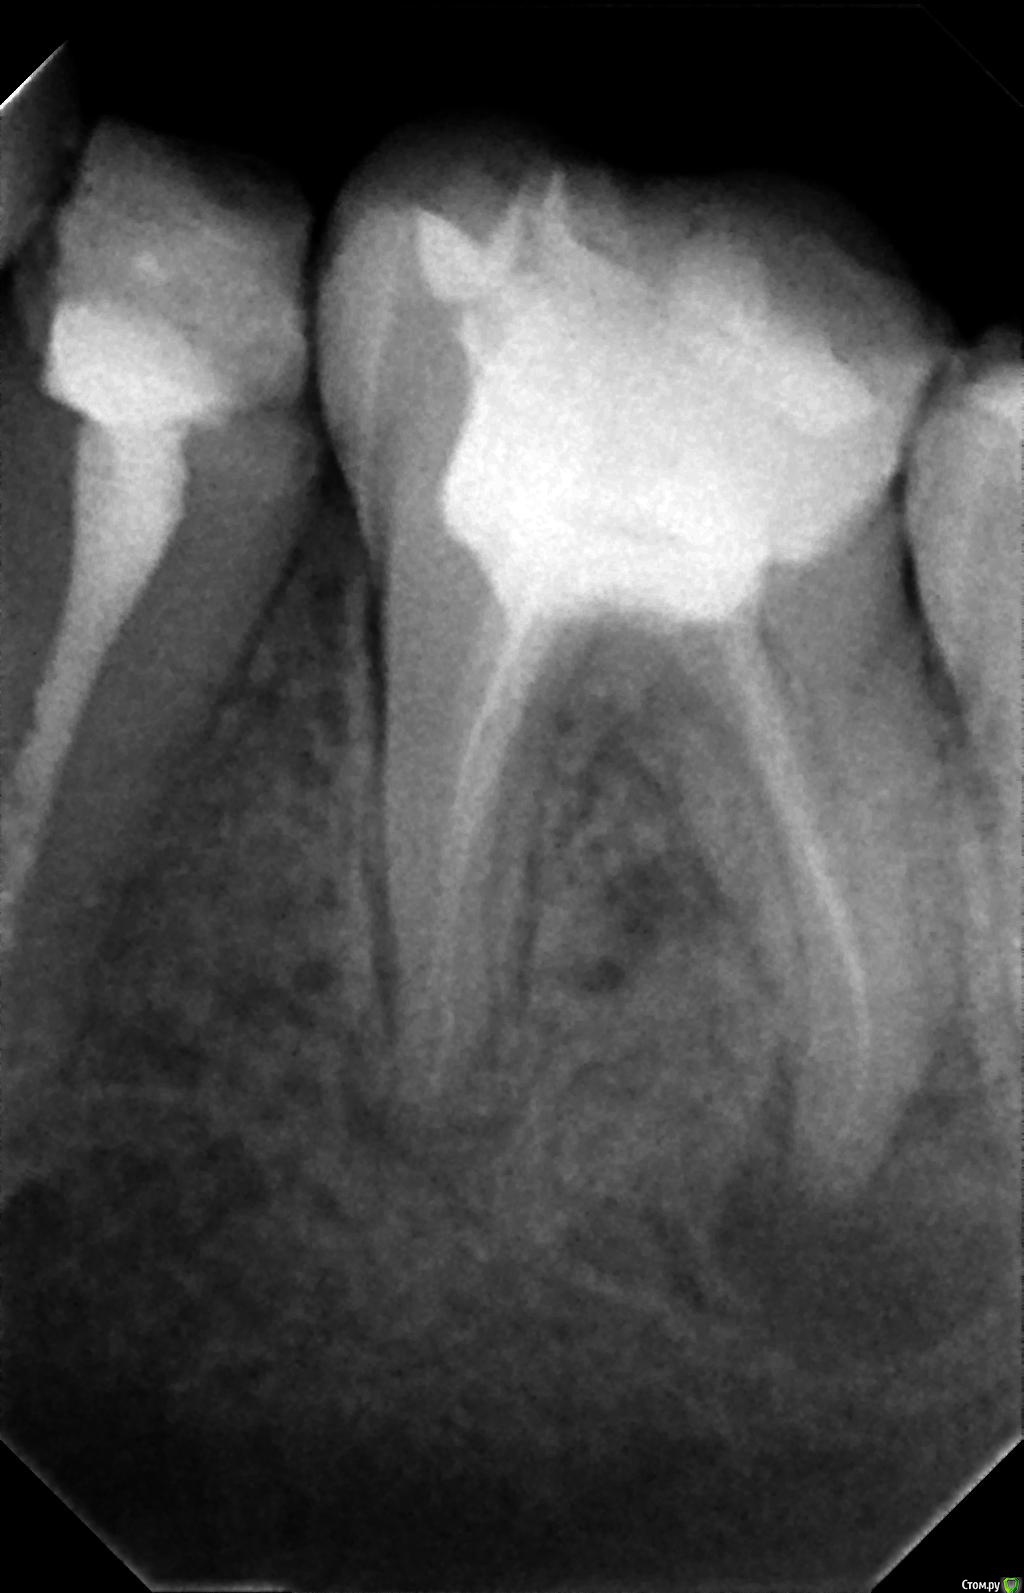

Ёлкаа Опубликовано 8 февраля, 2016 Поделиться Опубликовано 8 февраля, 2016 Добрый день!Помогите, пожалуйста, совсем не знаю, что мне делать.На "мертвом" зубе образовалась киста. В основном врачи рекомендуют удалить зуб.Подскажите, пожалуйста, есть ли возможность сохранить зуб или в этом нет смысла. Фото 5-ки, 6-ки и 7-ки прилагаю.Также в дальнейшем в планах ставить брекеты.Помогите, я совсем запуталась Заранее спасибо! Ссылка на комментарий

red_butler Опубликовано 8 февраля, 2016 Поделиться Опубликовано 8 февраля, 2016 Если судить только по снимкам, то лечить. Очный осмотр расставит все по местам. 1 Ссылка на комментарий

DmitrySH Опубликовано 8 февраля, 2016 Поделиться Опубликовано 8 февраля, 2016 Конечно лечить!Ничего очень страшного на снимках не вижу и в большинстве случаев такие зубы успешно сохраняются. Ссылка на комментарий